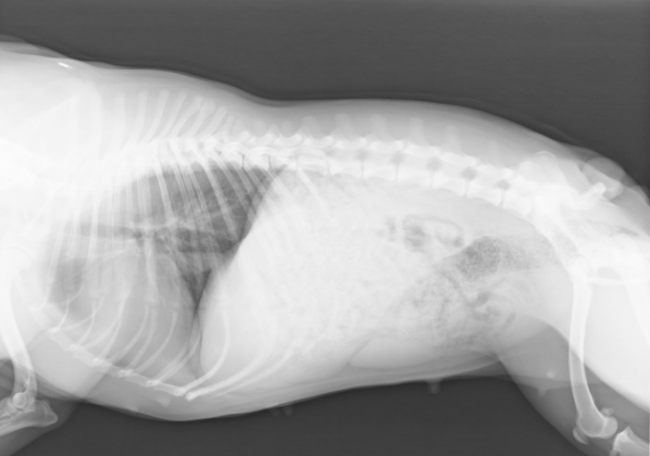

Arthrose Spondylose Definition. Eine Spondylose beim Hund bezeichnet eine degenerative, verschleißbedingte Veränderung der Wirbelsäule. Beim Hund handelt es sich meistens um eine sogenannte Spondylosis deformans, bei der es zu knöchernen Überbrückungen zwischen den Wirbelkörpern kommt.

Der Körper bildet knöchernes Ersatzgewebe was Reibung zwischen den Wirbelkörpern aber auch an der Faszialen Schicht verursacht. Daher ist eine Spondylosis deformans meist sehr schmerzhaft. Ist der Wirbelkörper aber erst einmal komplett verknöchert ist keine Bewegung dieses kleinen Teils der Wirbelsäule mehr möglich und der Hund hat wesentlich weniger Schmerzen da die Reibung nicht mehr statt findet.